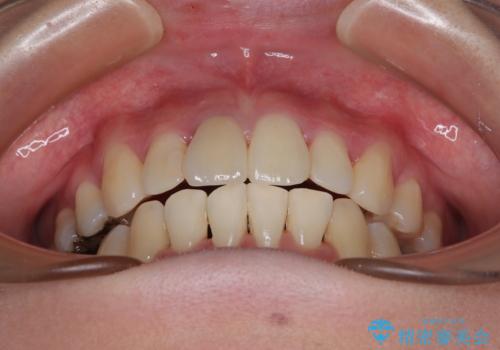

- 八重歯と上の前歯が出っ歯になっていることを気にして来院された患者様です。

横から見た際の口元の飛び出した印象も改善したいとのことで、上下左右の第一小臼歯4本を抜歯し、ワイヤー装置にて抜歯矯正を行うこととしました。

前歯の変色している歯は、神経組織が壊死していたため、矯正治療前に根管治療を実施し、矯正治療後にオールセラミッククラウンにて補綴治療を行うこととしました。